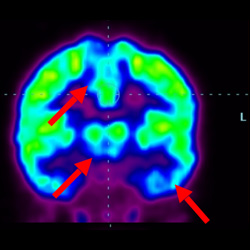

細胞治療前 PET CT 掃描顯示神經(jīng)組織中的藍/黑色區(qū)域,表明腦癱引起的大腦損傷。

腦癱細胞療法, 腦癱治療

細胞治療后,藍色和黑色區(qū)域減少,并且看到更活躍的區(qū)域。這表明損傷減少并改善了大腦功能。